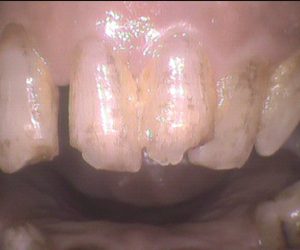

今日のクリーニングです。 クリーニング前 この方は約3年ぶりのクリーニングで、 下の前歯の間から根元にかけて歯石が多くついていました。 クリーニング後 […]